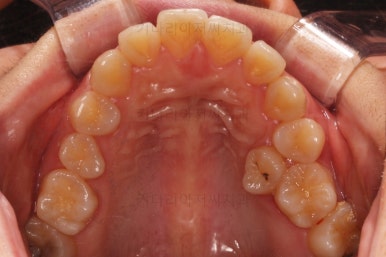

마찬가지로 부산연산동교정치과 초진 시 입안의 모습입니다.

눈에 띄는 것은 윗니 안쪽 치아 하나가 아예 입천장쪽으로 나서 매우 삐뚤어요.

저렇게 삼각혁으로 배치되어 있는 치아는 셋 중 하나는 꼭 썩어요.

셋 사이에 음식물이 잘 끼고 양치가 힘들기 때문이죠.

아래 앞니도 삐뚤한 편이었고 아래 앞니가 불쑥 위로 올라와 있어서 이를 악 다물면 위아래 앞니가 많이 겹치는 "과개교합" 패턴이 나타나요.

윗니가 전반적으로 아랫니보다 앞에 나와 있어서 2급 부정교합에 윗니만 튀어나온 양상이고 이 때문에 윗니 앞니가 다치고 부러졌따가 떼운 흔적이 보이네요.